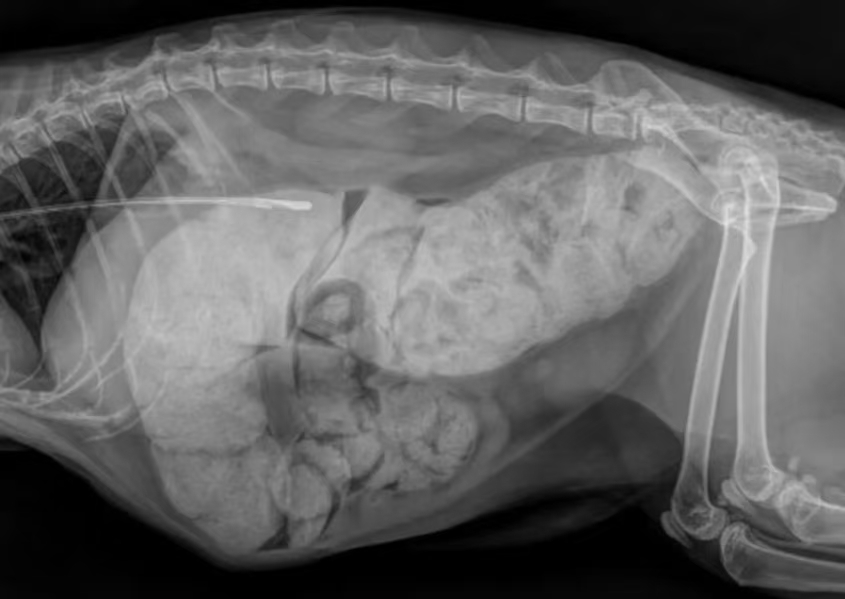

腹部高度膨胀,可触摸到大量坚硬粪块,结肠明显扩张,猫咪疼痛敏感,脱水严重,精神沉郁。 - 影像学检查(腹部X光)

X光片清晰显示:结肠极度扩张,充满大量干结粪便,肠壁肌肉失去收缩功能,确诊为重度猫巨结肠。 - 术前实验室检查